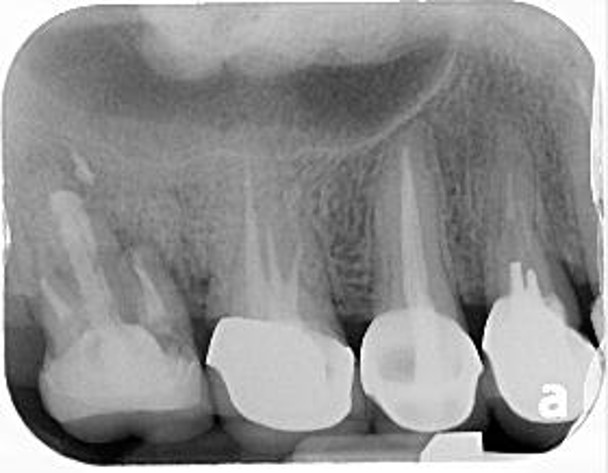

治療前,牙齒長膿胞

治療前,牙骨已破壞